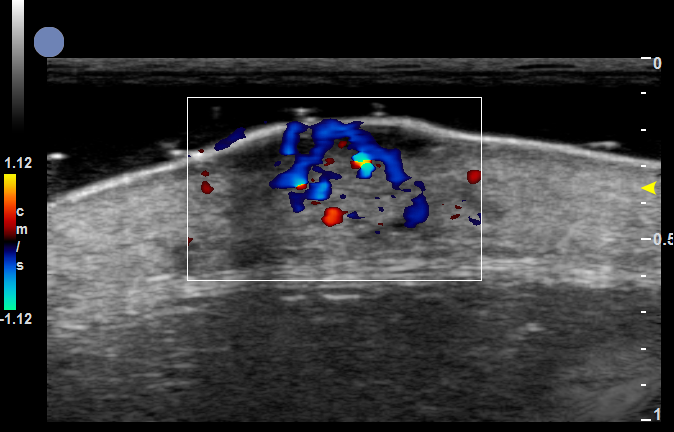

增殖期血管瘤